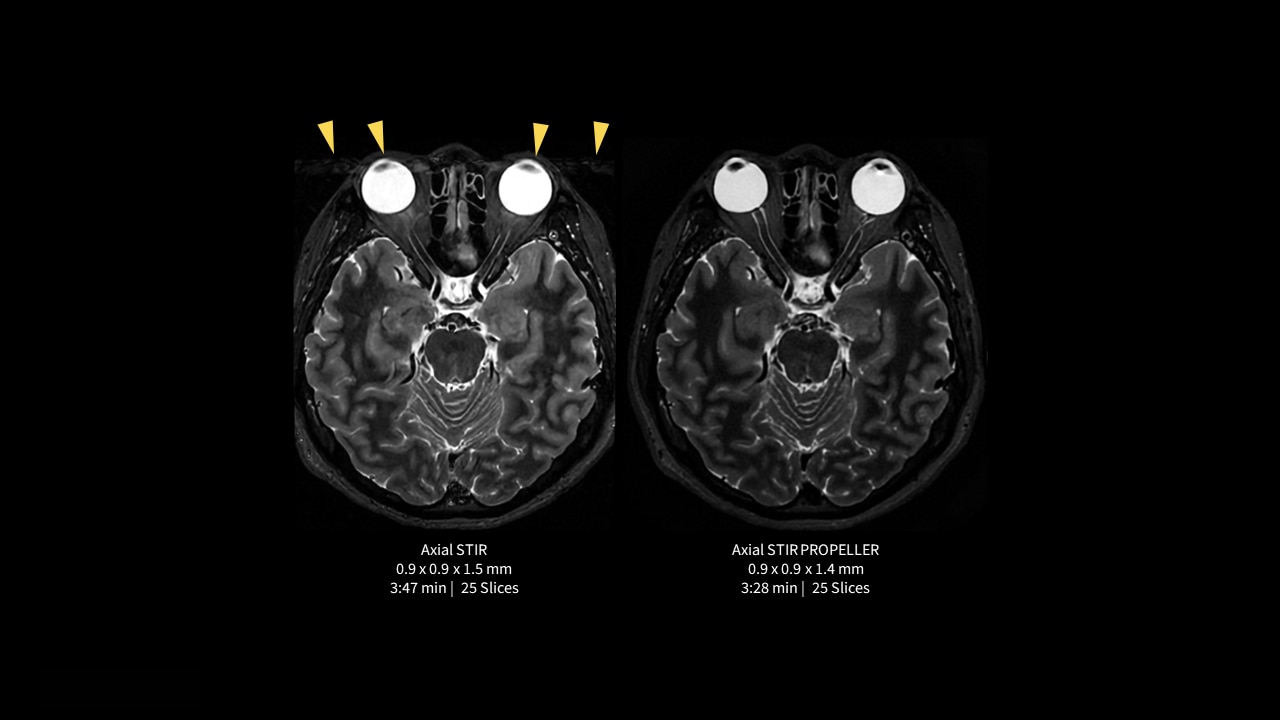

Generate consistently good, diagnostic-quality images even for challenging patients and difficult-to-image anatomies.

PROPELLER uses a radial k-space filling pattern that is inherently less sensitive to motion such as CSF and blood flow, breathing, patient tremor, or voluntary movements. The oversampling of the k-space center yields increased signal-to-noise ratio (SNR) and high tissue contrast. Scan time is the same as conventional techniques, and PROPELLER allows free-breathing acquisition.